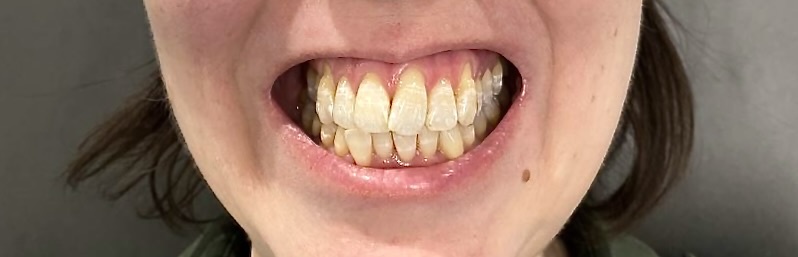

Дёсны ползут прочь от зубов, корни оголяются всё больше и больше с каждым днём и кажется, что зубы вымахали в длину, стали лошадиными какими-то. Страшно, что выпадут в один несчастливый день. Все. Разом.

Пациентка показывает зубы:

Действительно, рецессии серьёзные - корни оголены значительно, тут не скажешь, что ерунда. И, одно дело, если речь об эстетике идёт - тут каждому своё.

Страшно, что станет ещё хуже. И вот тут я не могу сказать, что такого не случится. Это патология и как она себя поведёт со временем, не может знать достоверно никто.

Даже человек, далёкий от стоматологии, заметит, что что-то не так. Узкие челюсти при крупных зубах, зубы стоят не в лучших своих позициях под не лучшими углами.